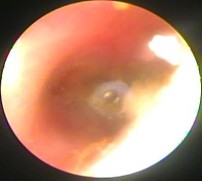

Ảnh 16 Màng nhĩ vôi hóa MSBA. 1806217639 | |